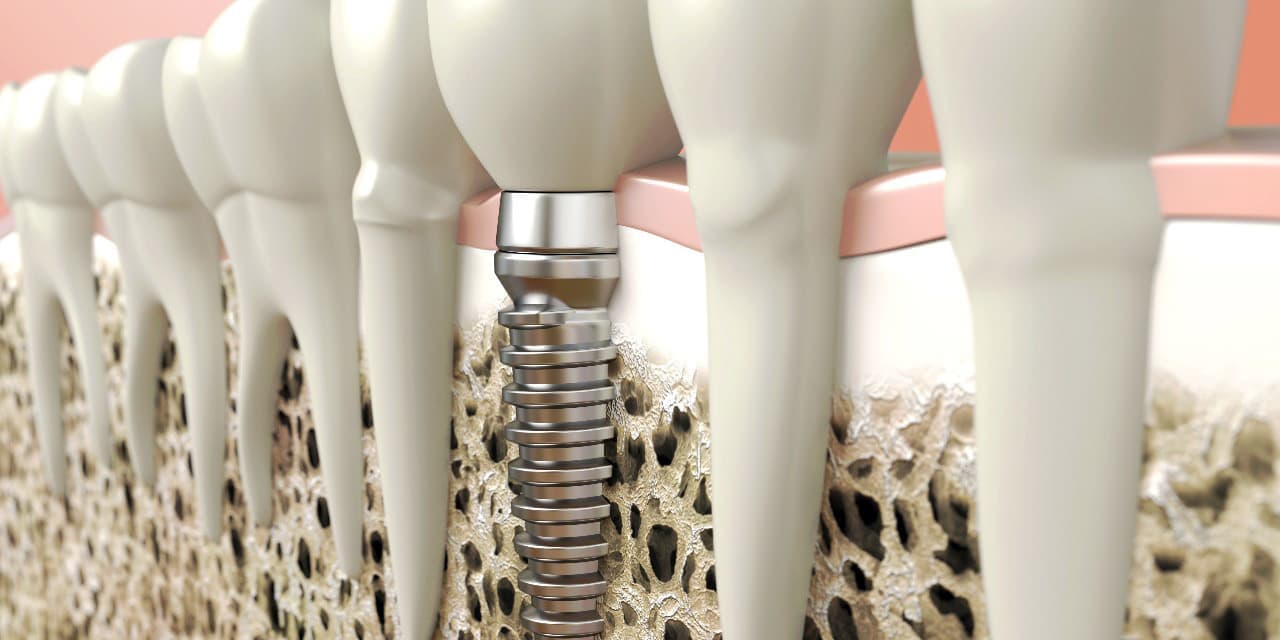

インプラントとは、顎の骨に人工歯根となる金属を埋め込み、その金属を土台にして、天然の歯と同じような人工の歯を取り付ける治療方法です。

埋め込む金属に生体との親和性が高いチタンが使われる事が多く、チタンは長年の臨床研究でインプラントの素材として最も安全であり、また顎の骨としっかり結合することが確認されています。